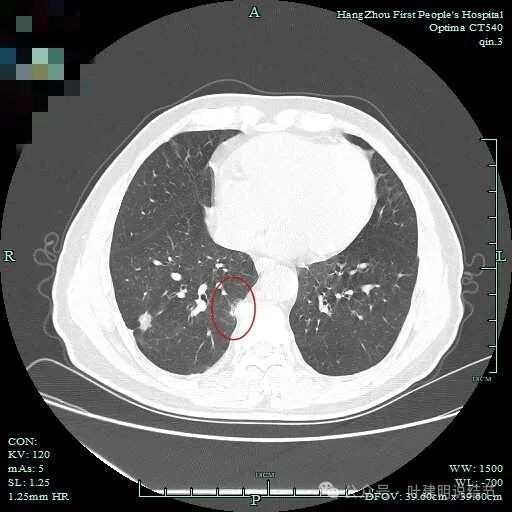

右下脊柱旁怎么也像有磨玻璃结节?但此处正常CT也是略显有慢性炎似的征象的,可这个病人明显结节状,还表面有细毛刺似的。

次病灶连续层面观察:

紧贴脊柱处混合密度,趴在脊柱上,这不像结节状。

但有小血管似的,磨玻璃部分界限较清。但此类异常影像在正常人的CT上也挺常见。

密度较高,确实像血管进入。但病灶片状,趴在脊柱上。